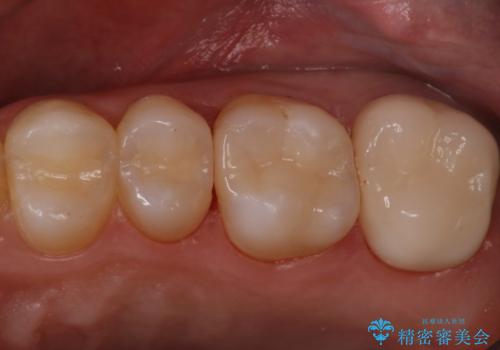

- 他院にて虫歯を指摘され、セカンドオピニオンを希望し当院へ来院されました。以前より磨きずらさと舌感の悪さは自覚していたそうです。清掃性、機能性に優れたセラミックインレーにて治療をすることとなりました。

レントゲンから昔詰めた保険の詰め物が入っていることが確認できました。詰め物と歯の隙間が虫歯になっていたためしっかり取り除き、適合の良いセラミックインレーを入れました。